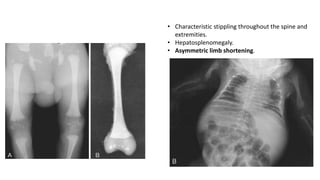

• Characteristic stippling throughout the spine and

extremities.

• Hepatosplenomegaly.

• Asymmetric limb shortening.